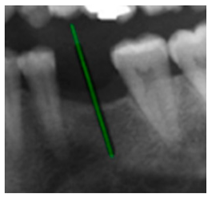

The angle bisector of the two auxiliary lines was then calculated using the angle bisector formula shown in (8), where (, , ) and (, , ) represent the coefficients of the two lines. The resulting internal angle bisector defines the preliminary implant pathway orientation derived by this framework. This bisector represents the most stable implant pathway orientation direction, ensuring that the implant avoids adjacent teeth and critical anatomical structures while maximizing bone–implant contact area. Such orientation enhances osseointegration stability and prevents complications from improper angulation, such as malocclusion or uneven stress distribution. The visualization of this process and the algorithmic design are presented in Figure 8. Finally, the auxiliary pathway generated by the algorithm was compared and overlapped with the implant pathway orientation annotated by dentists on the images to evaluate the predictive capability and accuracy of the model. The overlap results serve as a basis for further model optimization and provide valuable reference information for clinical application.

Figure 8.

Auxiliary lines are derived from adjacent teeth, the blue and yellow line is the result of implant pathway orientation visualization algorithm, and the green is the best implant pathway orientation.

3.3. Comparison with Clinical Ground Truth and AI-Assisted Framework

This subsection presents a comparison between the dentist-defined clinical gold standard and the predictions generated by our AI-assisted framework to evaluate the reliability of implant pathway orientation. The result is shown in Table 10, the preserved DPR validation set was used for verification, and the AI-assisted framework results were overlaid onto the original DPR images to provide a clear visualization. The AI-assisted framework pathways (green lines) were highly consistent with the dentists’ ground-truth annotations (black lines). Quantitatively, the mean squared error (MSE) between the predicted implant direction and the dentists’ planned results was only 1.537° across multiple test images. This minimal deviation validates the proposed system’s technical feasibility. It highlights its clinical potential to provide accurate and stable guidance for implant placement, thereby reducing the risk of misalignment and supporting efficient preoperative orientation.